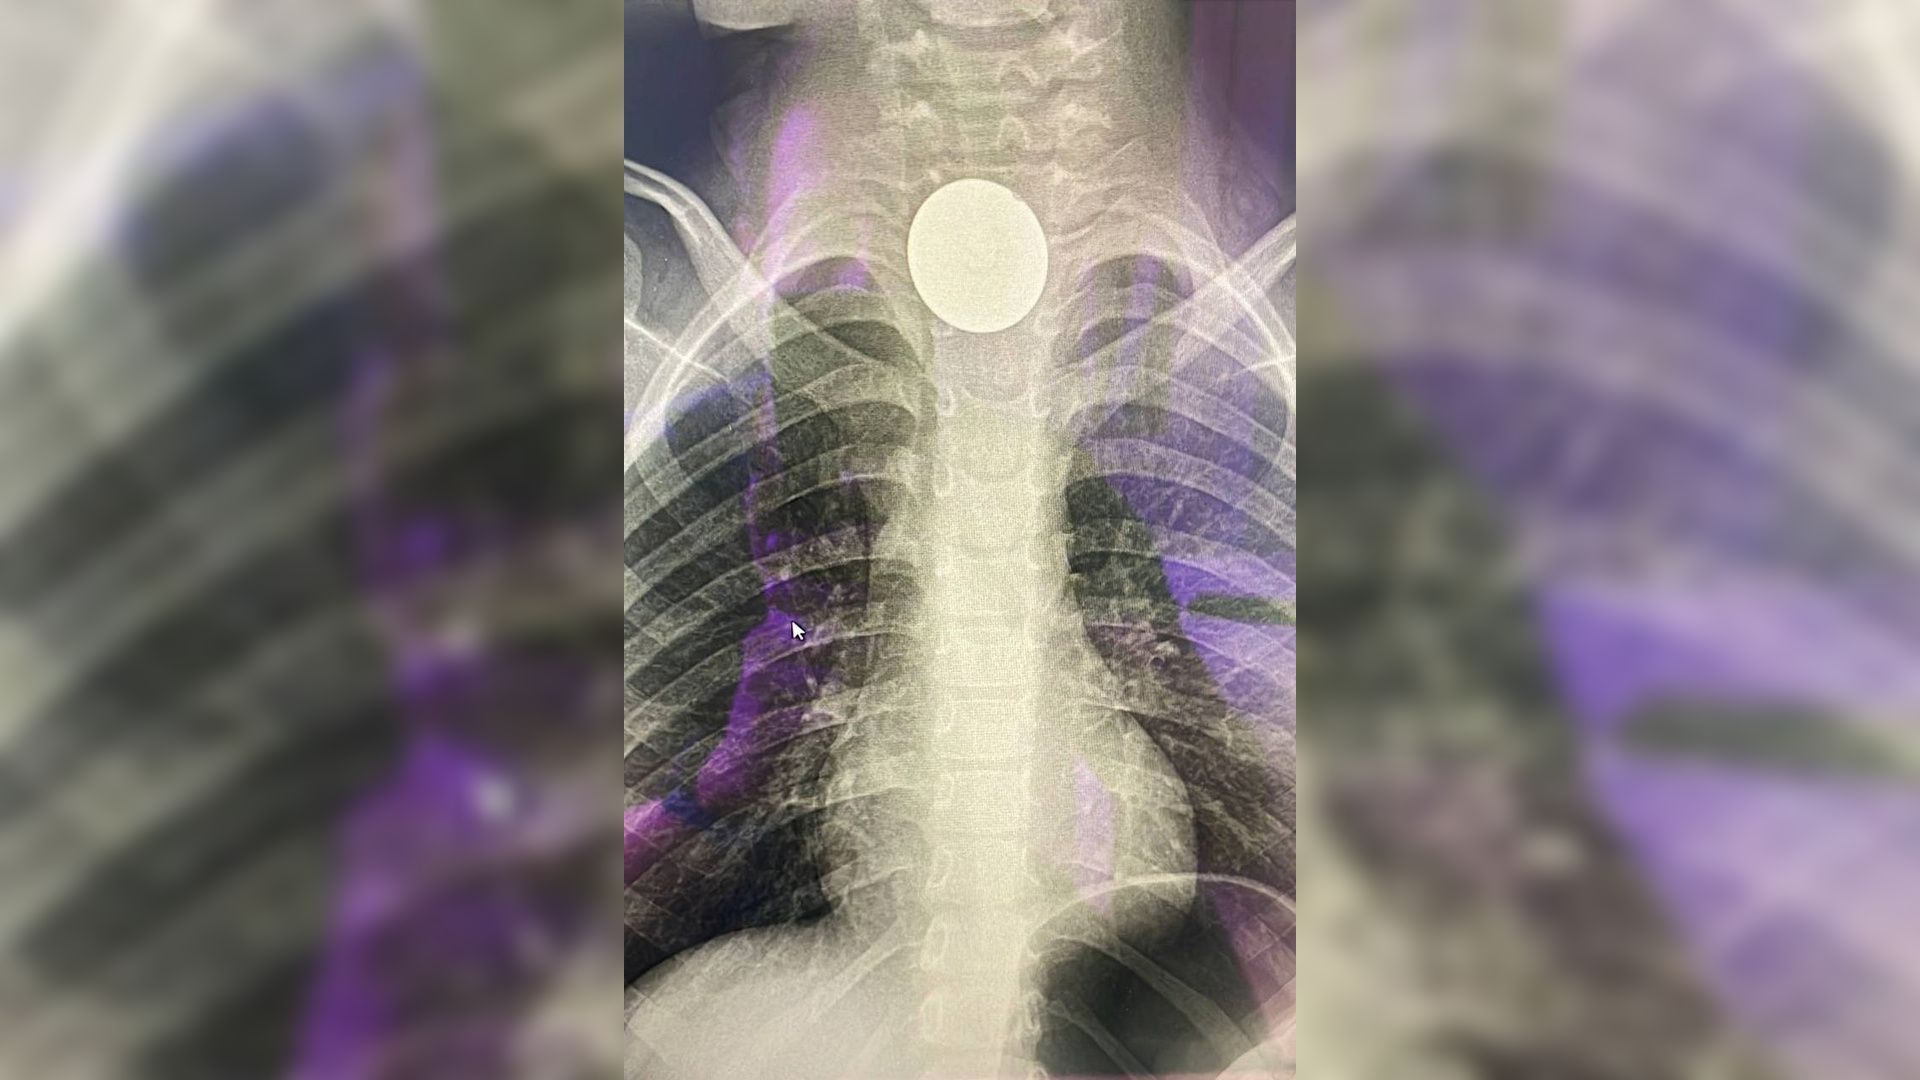

После резкого повышения температуры Максима госпитализировали с подозрением на инфекционное заболевание. Бдительные врачи ДГКБ № 5 имени Филатова решили сделать рентгенографию пищевода и обнаружили злополучную монетку.

Из-за длительного нахождения в слизистой монета вросла в ткани, вызвала воспаление средостения и нарушение проходимости. Хирурги провели экстренную операцию, после которой мальчик еще несколько дней провел в медикаментозном сне. Сейчас Максим в порядке и чувствует себя хорошо.